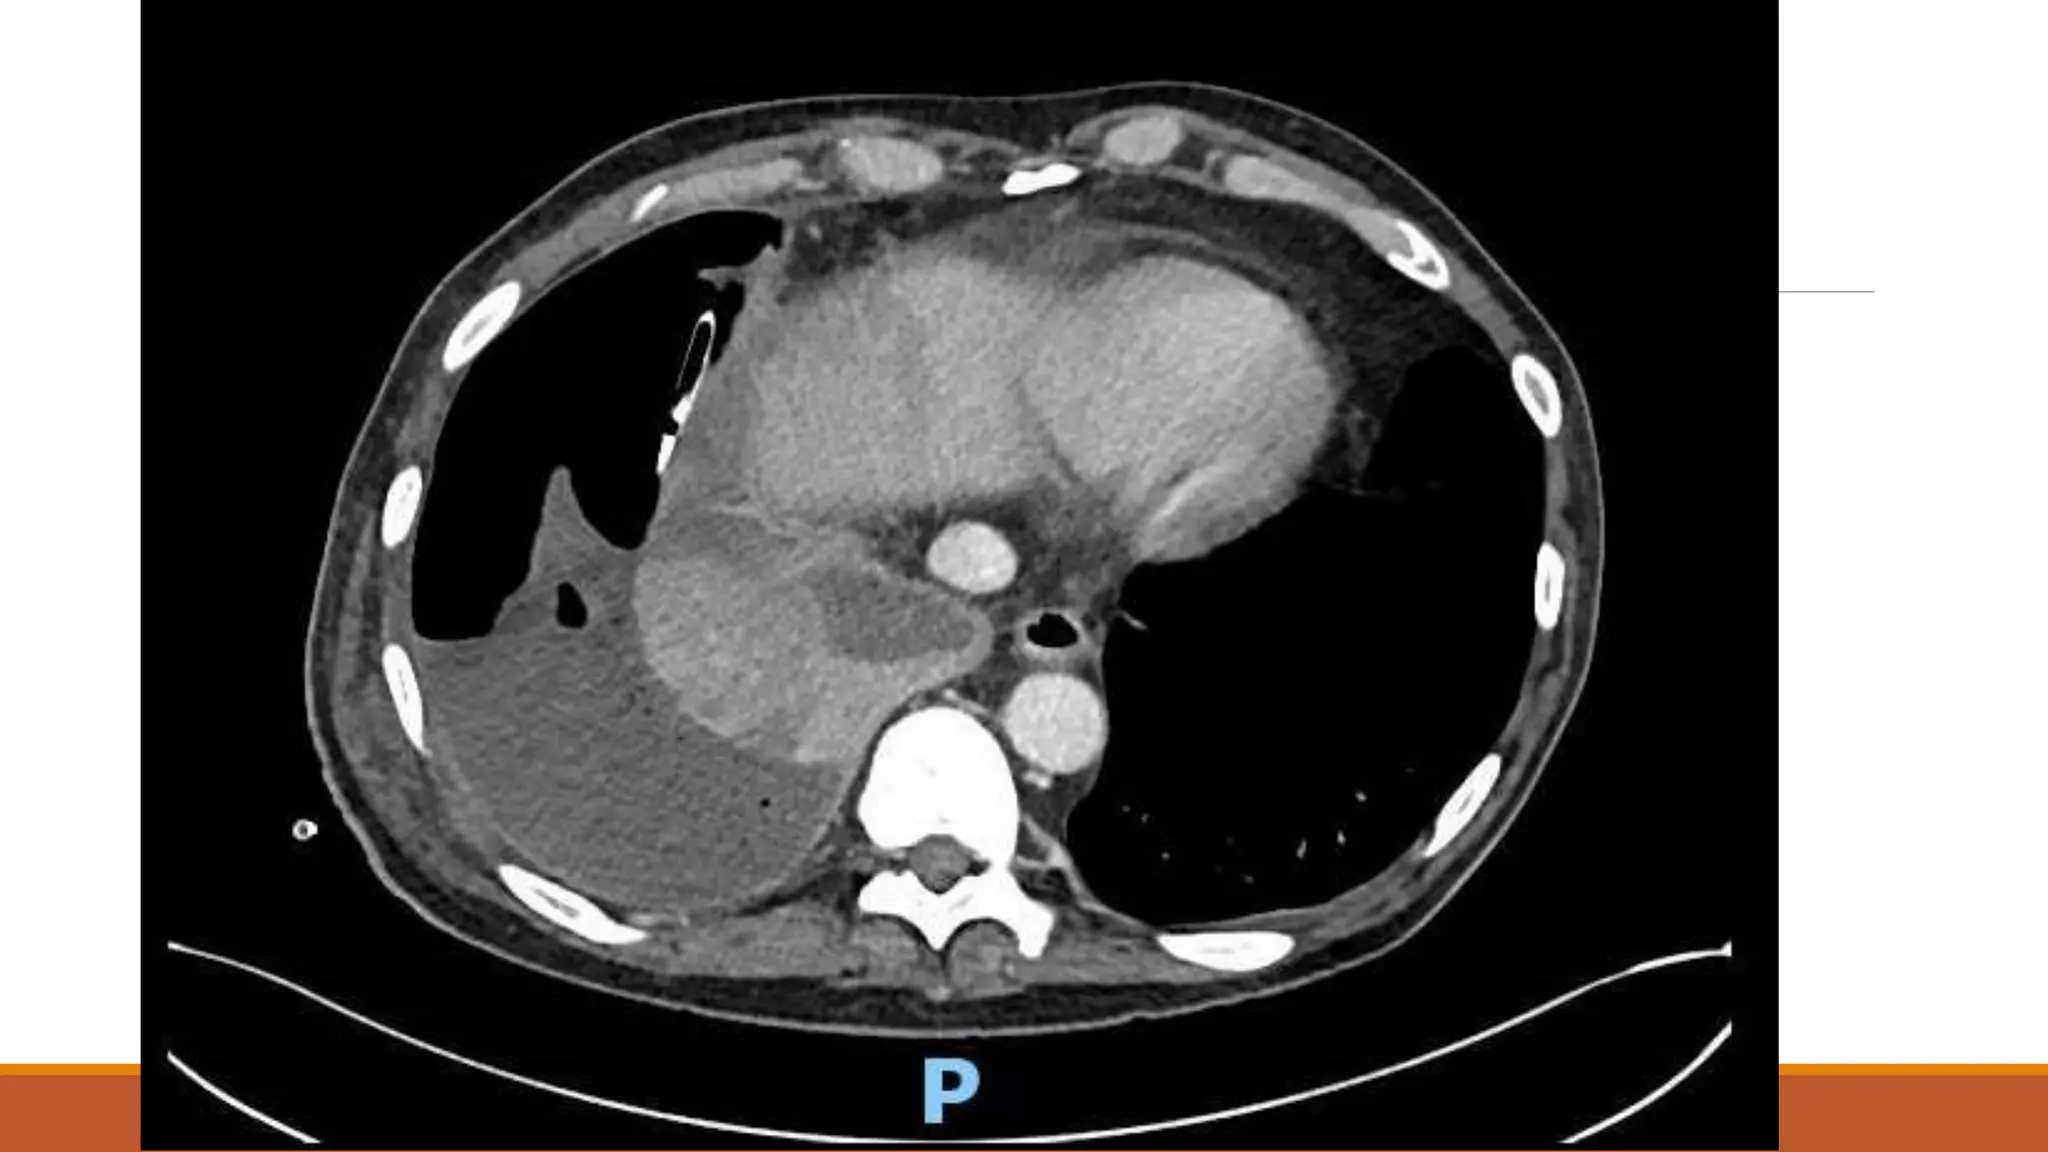

63 male

Normally F&W, no regular medications

Became unwell 7th Dec 2020 – cough, yellow sputum

Saw GP 23rd Dec – oral doxy

No real improvement – Clarithromycin 6/1/21

Again no improvement

Progressive loss of appetite and weight over a couple of months – given fortisip, which stopped

weight loss, but poor appetite continued

Progressive right shoulder pain and inability to lie on left side due to dyspnoea

On examination

OE: Acutely distressed, in significant pain and sats dropped to 80% when sat forwards, but 98%

when reclined at 60 degrees

Chest – no air entry right side